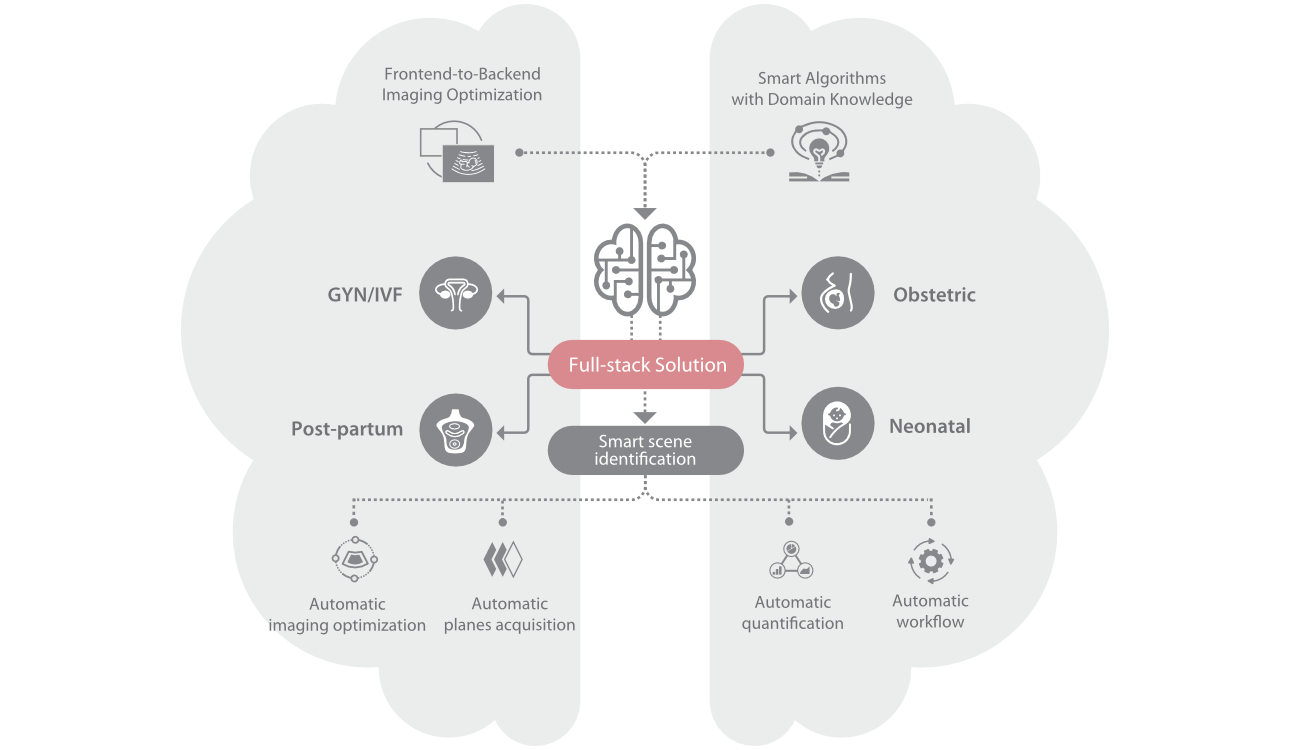

Nuewa I9, kad?nlara ve yenido?anlara y?nelik sa?l?k hizmetleri i?in ?zel olarak tasarlam??t?r ve i?ten d??a yenilik?i bir deneyim sunmaktad?r. Bu yenilikler, karma??k klinik senaryolara ili?kin derinlemesine bilgilere dayal? olarak geli?tirilmi?tir ayr?ca do?ru ve zaman?nda yan?tlar?n yan? s?ra, ola?an├╝st├╝ verimlilik ve ola?an├╝st├╝ kullan?c? deneyimi sunar.

ZST + Taraf?ndan Desteklenen Eksiksiz ??z├╝m

ZST+ platformu, ultrason evrimini temsil eden ola?an├╝st├╝ bir yeniliktir. Ultrason ?l?├╝mlerini geleneksel ???n bi?imlendirmeden kanal verilerine dayal? i?lemeye d?n├╝?t├╝r├╝r. Mekansal ??z├╝n├╝rl├╝k, zamansal ??z├╝n├╝rl├╝k ve doku homojenli?i aras?ndaki geleneksel dengeli s?n?rlaman?n ├╝stesinden gelir ve kesintisiz iyile?tirmelerle s?n?rs?z g?r├╝nt├╝leme ??z├╝mleri i?in ola?an├╝st├╝ g?r├╝nt├╝ kalitesi sunar.